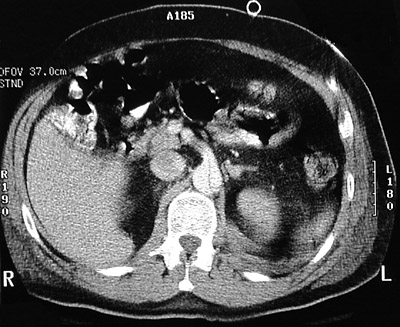

| These abdominal CT scan views above and below demonstrate an aortic dissection proceeding to the descending aorta. The superior mesenteric artery branch also appears to be affected. The classic historical finding of sudden, severe, "knife-like" pain in the chest or upper abdomen is more likely to be present in this situation. |